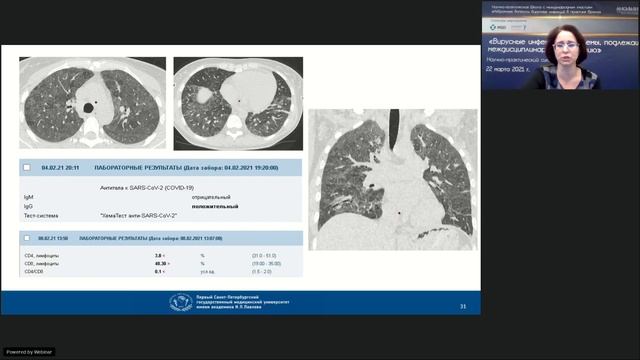

В рамках Научно-практической школы с международным участием – «Избранные вопросы вирусных инфекций в практике врача» прошел Научно-практический симпозиу...